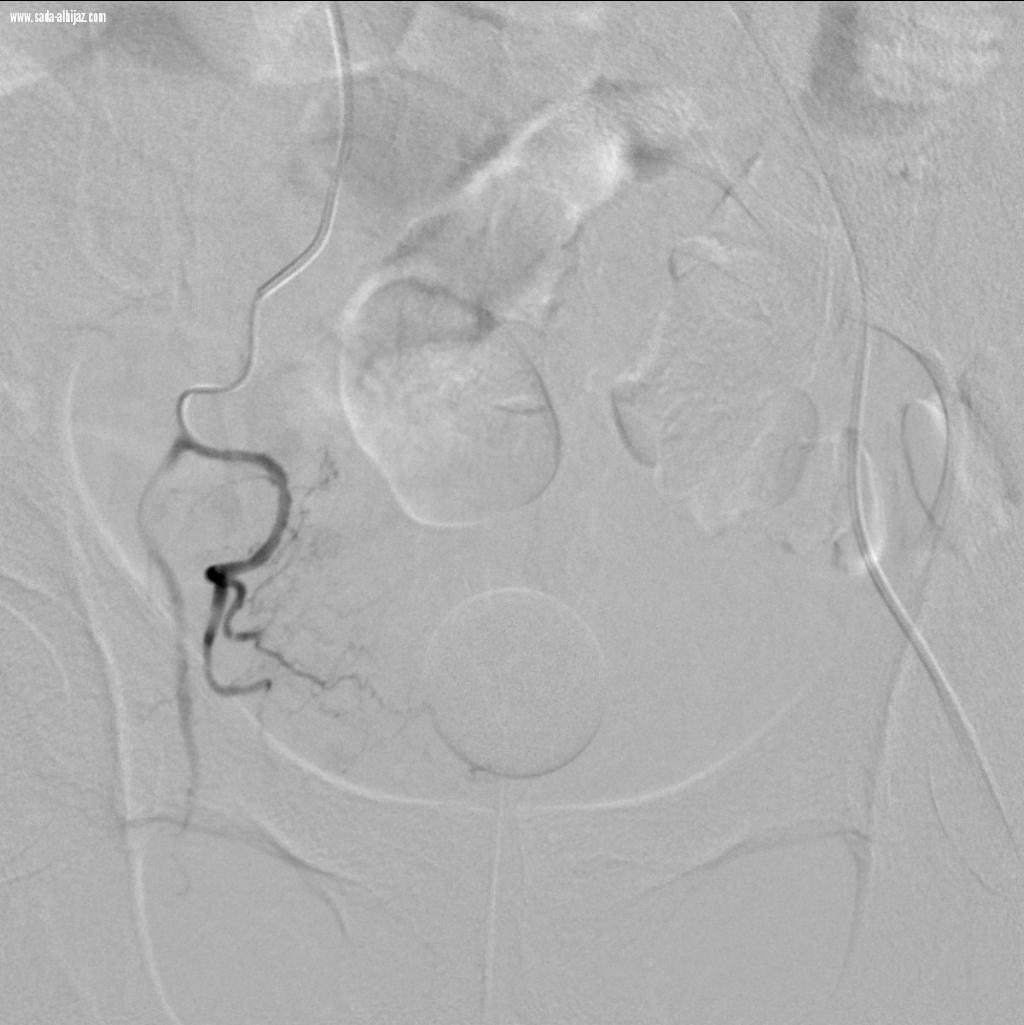

نجح بفضل الله فريق وحدة الأشعة التداخلية بمستشفى النور التخصصي بمكة المكرمة بالتعاون مع قسم جراحة المسالك البولية في إدخال خدمة جديدة و هي علاج تضخم البروستات الحميد المؤدي إلى إحتباس البول عن طريق الأشعة التداخلية.

و نظراً لحالة المريض الصحية و التي تجعل من الجراحة التقليدية إجراء عالي الخطورة فقد تم تحويل المريض لأطباء وحدة الأشعة التداخلية و الذين قاموا بمعاينة المريض و مراجعة الفحوصات و عمل الأشعات اللازمة و من ثم اجراء العملية التداخلية بإستخدام التخدير الموضعي فقط .

تجدر الإشارة أن هذا الإجراء الطبي يعتبر أحد الاجراءات الطبية الحديثة و المثبتة علميا بمنفعتها لمثل هؤلاء المرضى